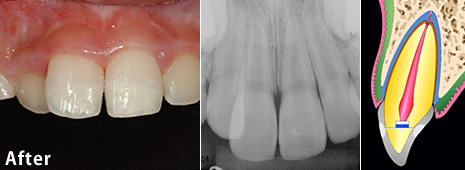

歯冠破折の治療例 その1

歯冠破折の治療例 その1 術前

術前:

12歳の少年の歯がけがで折れ、歯の神経(歯髄)が露出していましたが、歯髄は生きていました。

歯冠破折の治療例 その1 術後

術後:

見えていた歯髄の表層をとり(断髄し)、歯髄の傷が治りやすい薬で傷口を保護しました。その後、折れた破折片を、修復材にてもとの歯に接着しました。